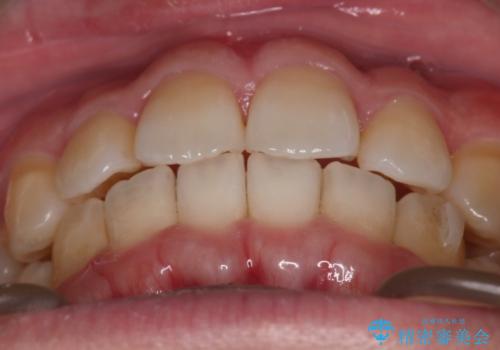

上の前歯が出ているという主訴が綺麗に改善されました。

その他の部位のがたつき、奥歯の噛み合わせも以前と比べると良くなっています。

目立たない装置で治療期間も10ヶ月と短く終了することができました。